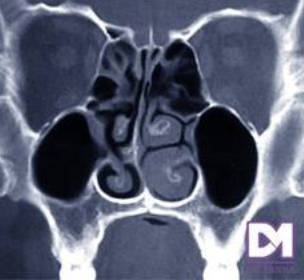

Cornete medio paradójico FP

16

Concha media bulosa

Desviación del tabique nasal

Siempre que veamos corte coronal buscar complejo osteo-meatal donde se observa la crista gali.

TECHO DE INFUNDIBULO ES CELDILLA ETMOIDAL: EN UN ADULTO SANO PUEDE MEDIR HASTA 4MM DE DIÁMETRO.

Cuando hay bloqueo anatómico en infundibulo estan fregados los senos frontal, etmoidal y maxilar

IMAGEN DE OCUPACIÓN PARCIAL EN SENO MAXILAR DERECHO DE UN 30% DE OCUPACIÓN. PERIFERICO, MARGINAL. CONDESVIACIÓN SEPTAL A LA DERECHA DE CONFORMACIÓN ÓSEA (PORQUE SE VE BLANCO)

SE OBSERVA HIPERTROFIA DE CORNETE INFERIOR IZQUIERDO. SUPERFICIE FESTONEADA: DEGENERACIÓN PÓLIPOIDEA.

CONCLUSIÓN: SINUSITIS MAXILOETMOIDAL BL, DESVIACIÓN SEPTAL E HIPERTROFIA DE CORNETE INFERIOR IZQUIERDO CON DEGENERACIÓN POLIPOIDEA.